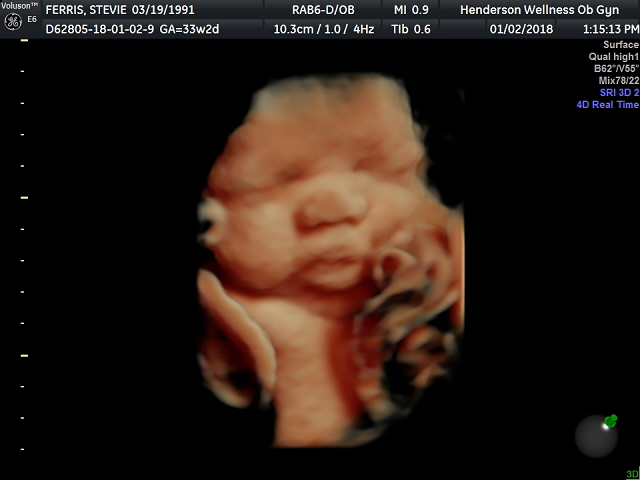

3d Ultrasound Las Vegas Nv

Difference Between 3d Ultrasound Scans And 4d Ultrasound Scans By

3d Scanner Image 3d Sonogram